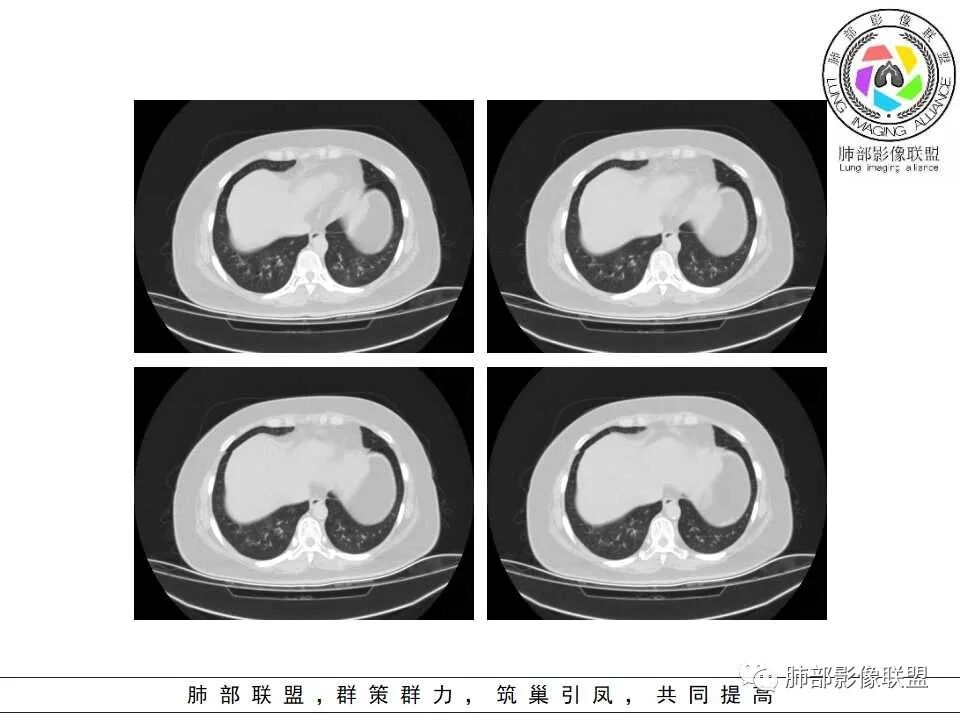

支气管壁增厚、毛糙,考虑气道侵袭性曲霉。

病史+支气管壁增厚+支气管肺炎影像病理基础的苏联红色革命+气喘=气道侵袭性曲霉

弥漫性支气管壁增厚,结合气管镜及痰鸣音,考虑气道曲霉

慢性病程,双肺支气管管壁增厚,周围可见多发点片状高密度影,边缘模糊不清,考虑气道侵袭性曲霉菌病

两肺支气管管壁增厚,沿支气管斑点状及斑片状高密度影,边缘模糊,考虑气道侵袭性曲霉菌,鉴别金葡萄、铜绿

居住地长年潮湿,老年女性,两肺支气管管壁增厚明显,考虑气道侵袭性曲霉菌,鉴别结核。

沿支气管血管束走形,气道壁增厚,边缘模糊,考虑考虑气道侵袭性曲霉,鉴别淋巴瘤。

中老年女性,气道分布的病变,有树芽树雾征,有支气管粘液栓,还有支气管壁增厚,考虑感染性病变,ABBA可能性大,鉴别支原体及军团,支原体以小孩多见,症状轻影像重,发病年龄及影像都不符合,患者住一楼,开麻将馆有聚集性,场地潮湿,不能排除军团肺炎!综合考虑ABBA,不排除军团

双肺沿支气管束见多发斑片状高密度影,界不清,支气管壁增厚,糖尿病史+环境因素,考虑IPA

双肺支气管血管束增粗,边缘模糊呈晕状,沿中轴间质走行分布多发斑片状影,边缘模糊,糖尿病人,血象高,G实验高,气道侵袭为主,考虑曲霉菌感染,鉴别金葡

老年女性,糖尿病,高血压,心功能不全,双肺支气管壁增厚,沿支气管血管束分布结节状、片絮状模糊影,麻将馆、潮湿环境工作,考虑感染性病变,曲霉菌?

月亮圆了!:

糖尿病,血糖控制不好,气促,炎症反应明显(白细胞,crp明显升高,Gm(+)。气道分布的结节磨玻璃密度影,树芽,气管壁增厚。曲霉的可能最大

1.病灶沿支气管分布的特点相当明显,相应支气管壁广泛增厚。这种与支气管关系极为密切的片影和/或结节影,常高度提示气道相关感染,如支气管肺炎。

3.支气管壁广泛增厚对气道侵袭性曲霉病具有一定的提示意义。注意患者没有支气管扩张,临床也未提供IGE等实验室资料。

一,气道侵袭性曲霉病(PNTA)

1.器官支气管管套样壁增厚和/或支气管扩张,注意壁增厚较均匀,和/或伴有播散性小片影及结节影,注意这些小片影或结节影边界有时较普通炎性病灶清楚。